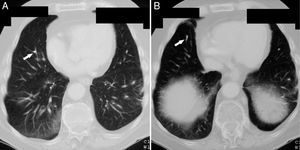

Vertebroplasty was performed in July 2007 and during the procedure surgeons detected a small cement leakage into the vena cava and the right pulmonary artery. The patient remained asymptomatic after vertebroplasty, without developing signs of hypoxemia and pulmonary hypertension. However, the control chest X-ray after the procedure showed radiopaque lesions on the vessels of the lower third of the right lung, which on CT corresponded to multiple emboli of cement in the distal branches of the right pulmonary artery in the middle and lower lobes (Figs. 1 and 2). The patient had no pain after the procedure and was asymptomatic from the respiratory standpoint; however, the cement emboli remained unchanged and are still observed in radiological controls to date.

Because CPE after vertebroplasty is not a rare event and since most cases are initially asymptomatic, the routine performance of a chest X-ray is recommended after the procedure, and even the performance of CT scans for early detection of cement emboli in the pulmonary circulation. In X-rays such emboli may be seen as multiple tubular or branched radiopacities. Computed tomography is the test of choice to confirm their presence, distinguished from other calcified lesions due to their location in areas of branching and the accompanying high attenuation areas around the pulmonary arteries. Echocardiography may be useful in assessing the development of pulmonary hypertension in patients with symptomatic or multiple emboli. In these patients, respiratory function tests may also show decreased CO2 lung diffusion capacity.20